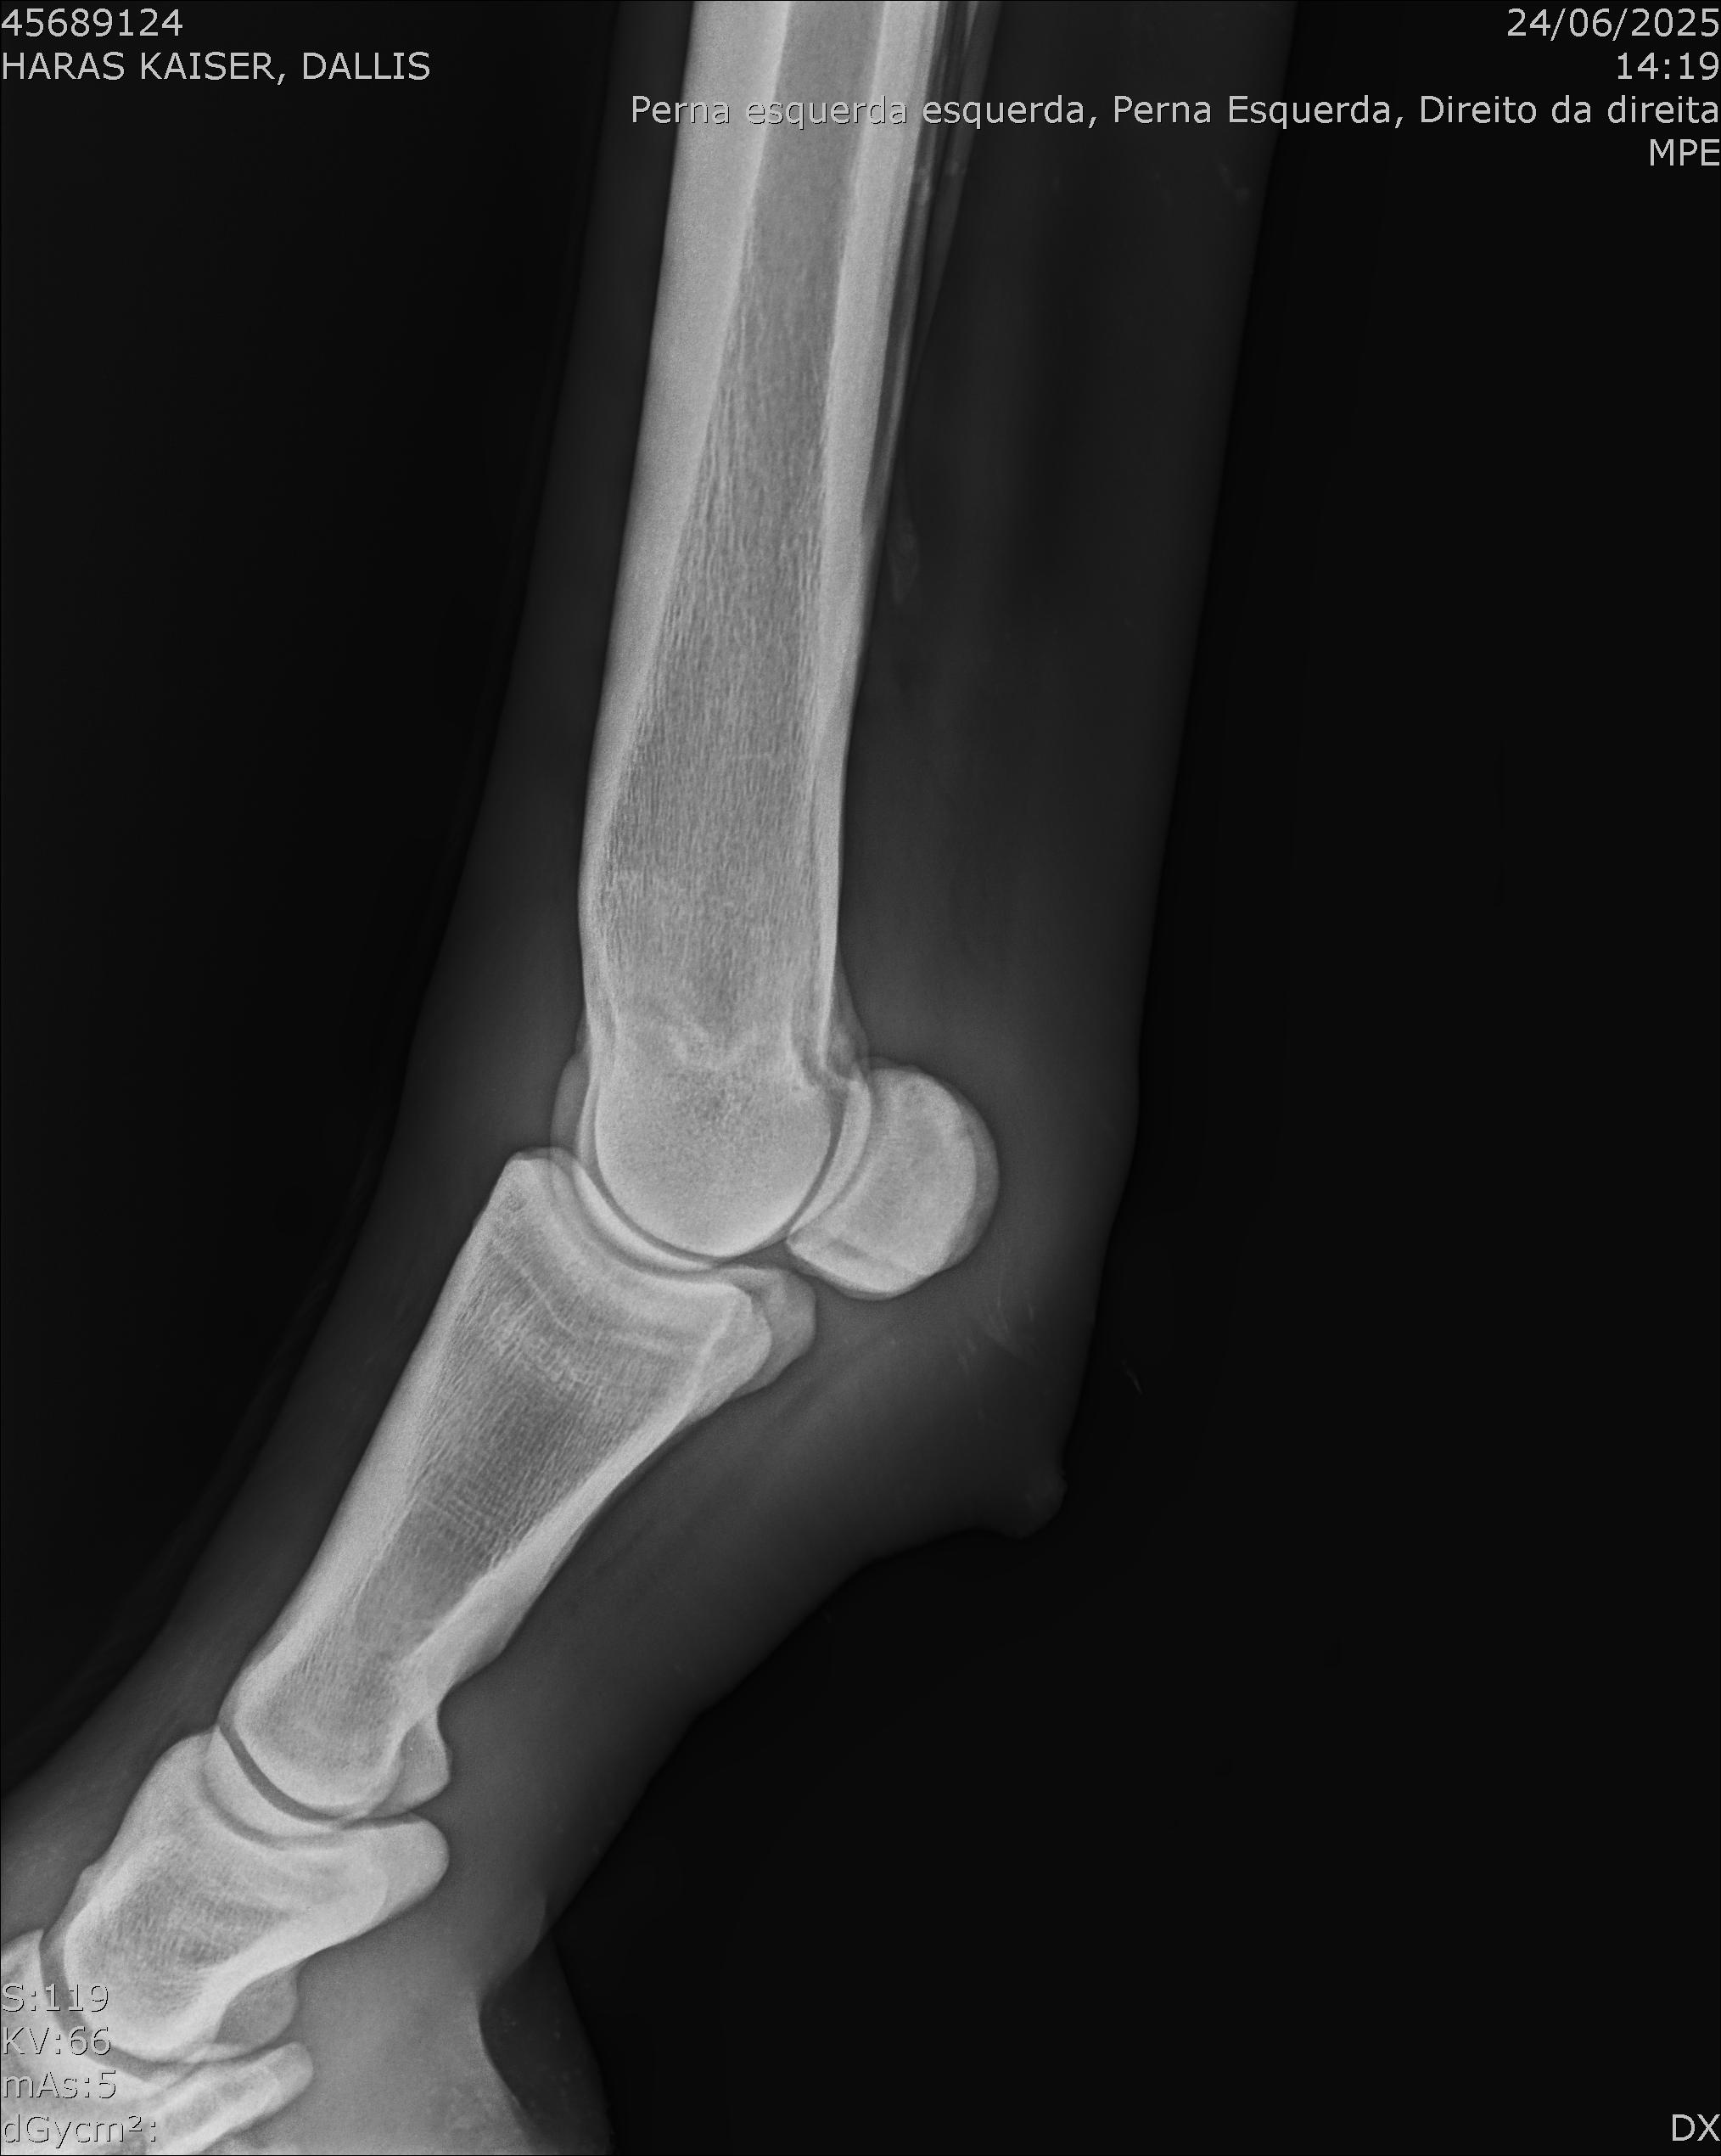

:: RAIOS-X DO LOTE